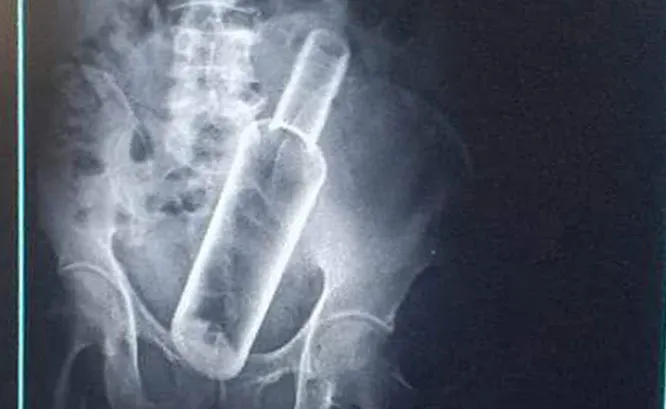

बिहीबार पेट दुखेर उपचारका लागि अस्पताल गएका कैलालीको धनगढी–१४ का ६१ वर्षीय जवानसिंह रोक्का मगरको पेटमा ८८४८ भोड्काको बोतल देखिएको हो ।

उनको पेटभित्र रक्सीको बोतल कसरी पस्यो भन्ने खुलेको छैन । उनले भने मदिरा सेवन गर्दा साथीले मलद्वारबाट पेटमा बोतल घुसाइदिएको चिकित्सकसँग भनेका छन् ।

यसअघि रौतहटमा पनि यस्तै घटना भेटेको थियो । भिडियो एक्स रे गर्दा एक युवकको पेटमा पनि यस्तै बोतल भेटिएको थियो । उनको चितवनको भरतपुरस्थित पुरानो मेडिकल कलेजका चिकित्सकले शल्यक्रिया गरेर पेटबाट बोतल निकालेको थियो ।